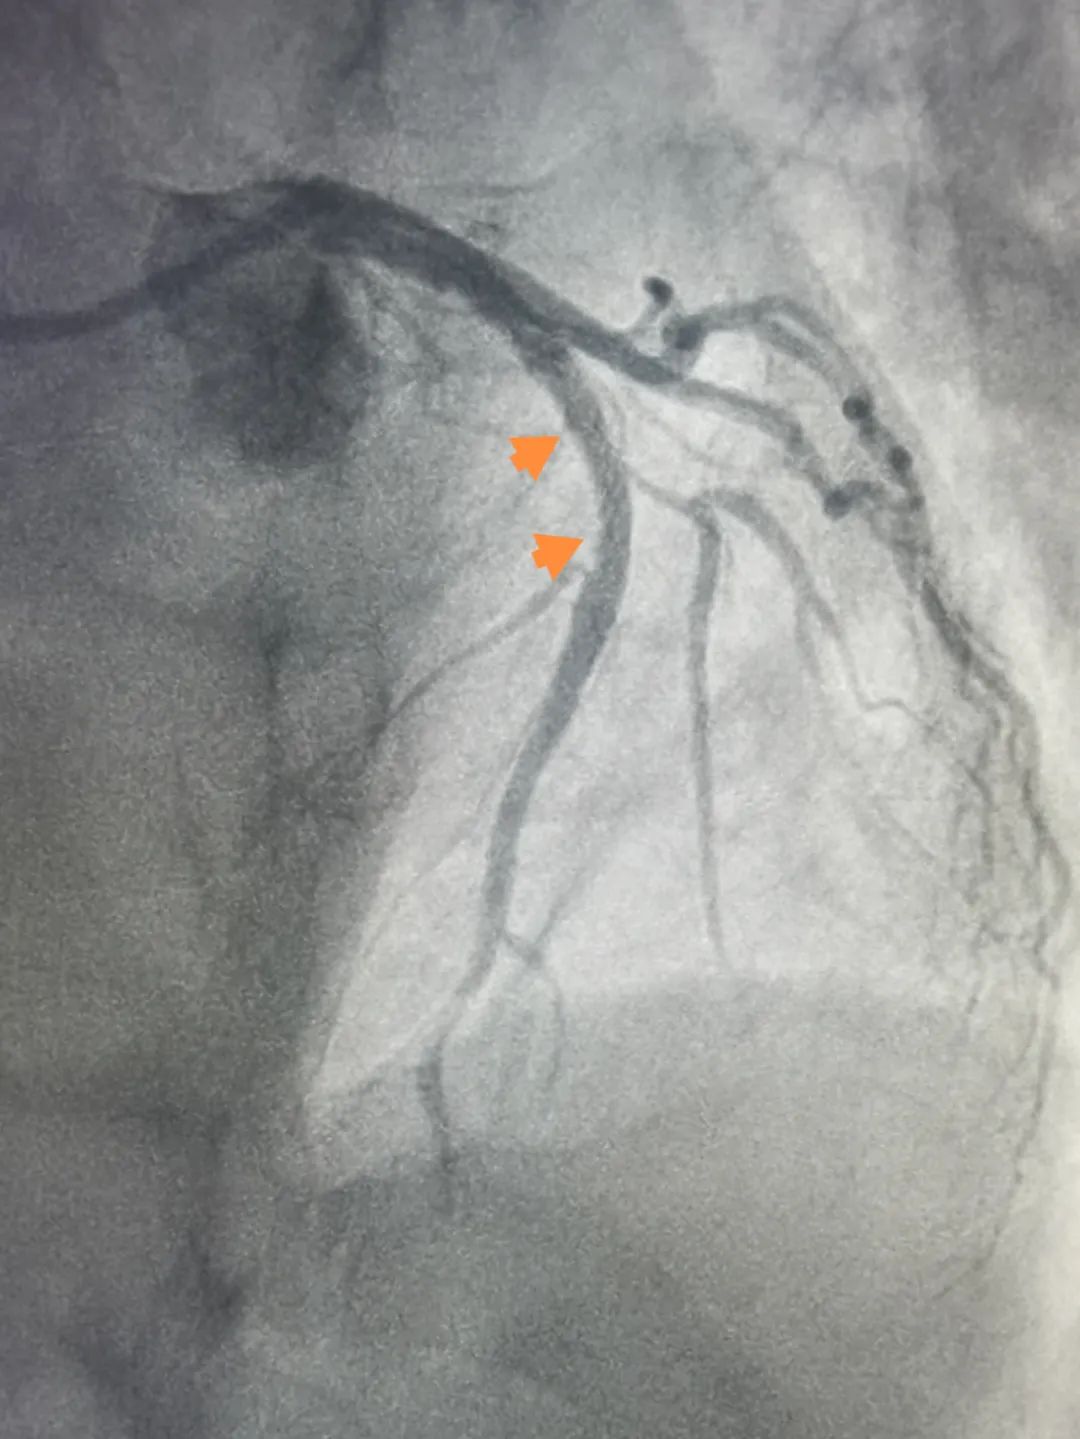

16:24在医生精确操作下导丝通过“罪犯血管”前降支;

17:17前降支植入支架1枚;手术成功完成,患者张大哥安返心血管内科重症CCU病房。